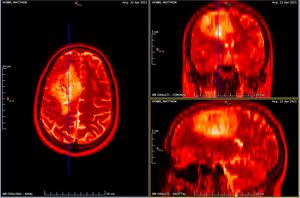

Obtained my full scan data - Tuesday 25th May

I received an automated email saying this could take up to 28 days, but 2 days later I had an email from a member of the team saying that my scans were scheduled for the overnight upload and I'd receive the link the following day. Upon receiving the link they sent me a one time password (OTP) via my mobile number that allowed me to login. The web performance of the system was shocking. Took around 20 seconds to load on a 50 Mbit connection and a modern browser! Thank you JavaScript...

The reason the zip file is so huge is because it is sent in a standardized format for use in specialist tools that can interpret the data. Here's me thinking it would be just a few images... nope! It's literally all the images from all scans completed so far! Hence the box on the form stating which scans you require.

I believe there are around 4,000-5,000 images in total from 1 CT and 1 MRI scan! Thankfully there are tools that you can use to view these images. And not just view them, they allow you to navigate through all the scans. Each image is essentially a "slice" of the brain. The tools allow you to move through all 3 axis in near real time, with each of the corresponding panels changing depending on the input from the others.

In the above image you can see my MRI scan. It's essentially an orthogonal view of my head, with each of the panels represents a different axis:

- Left panel: Top of my head (Axial view)

- Top right: Front to back of my head (Coronal view)

- Bottom left: Side of my head (Sagittal view)

The solid blue line you see in the views is the current plane I have selected to see. As you move this plane, all three images change accordingly. Notice how the blue line on the axial view (left panel) matches that of the coronal view (top right) in terms of position. The resulting image in the sagittal view (bottom left) is the image that corresponds with this selection I have made.

It's so incredibly clever and absolutely fascinating (to me at least)! I spent the best part of 2-3 hours looking at my own brain scans. I wish I knew what it all meant, but I plan on quizzing the experts when I get the chance. I'd like to write a blog post all about it in the future. So, watch this space!

For those interested in doing the same the tools I used are:

Horos takes it a step further, as it allows you to view your scan in 3D, and even export an animation to show all your friends at the next soirΓ©e you attend! So yes, if you ever fancy looking at your own insides in detail, remember you can request your CT and MRI scan data!